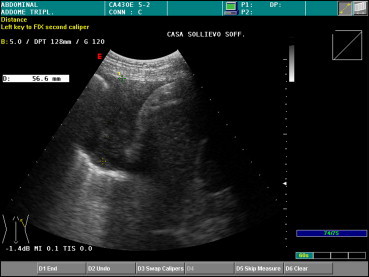

Thoracic US is the “gold-standard” method for studying pleural effusions [9]. It is more sensitive than chest radiography or CT in the detection of small amounts of pleural fluid (less then 10 ml) (Fig. 3). Effusions appear as a sharply demarcated, dark or echo-free zone image associated with downward displacement of the pleural line. The underlying lung may be well aerated, consolidated, or atelectatic [10]. Various formulas have been elaborated to estimate the volume of a pleural effusion and of atelectatic lung tissue and to identify the characteristics of the pleural fluid. In routine, daily practice, we usually measure the maximal longitudinal and transversal diameters of the effusion [11].

Fig. 3.

A longitudinal-oblique posterobasal US scan reveals a small effusion in the left costodiaphragmatic recess.